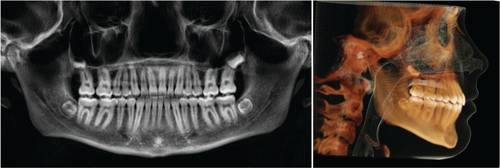

Fig. 3: Pretreatment OPG and lateral cephalogram

In 2019, CBCT imaging was added to enhance diagnostics, especially for airway evaluation, skeletal patterns, and root positioning. By 2020, we had fully embraced a custom-only approach with the LightForce system. Having braces designed around my treatment plan—not the other way around—gave me a level of control and precision I hadn’t experienced before.

Ruby, a 14-year-old female patient, presented with crowding of the upper incisors, Class II malocclusion, over-retained primary second molars, a midline discrepancy, and narrow arch forms (Figs. 1–3). We initiated treatment using the LightForce system, combined with remote monitoring through DentalMonitoring.